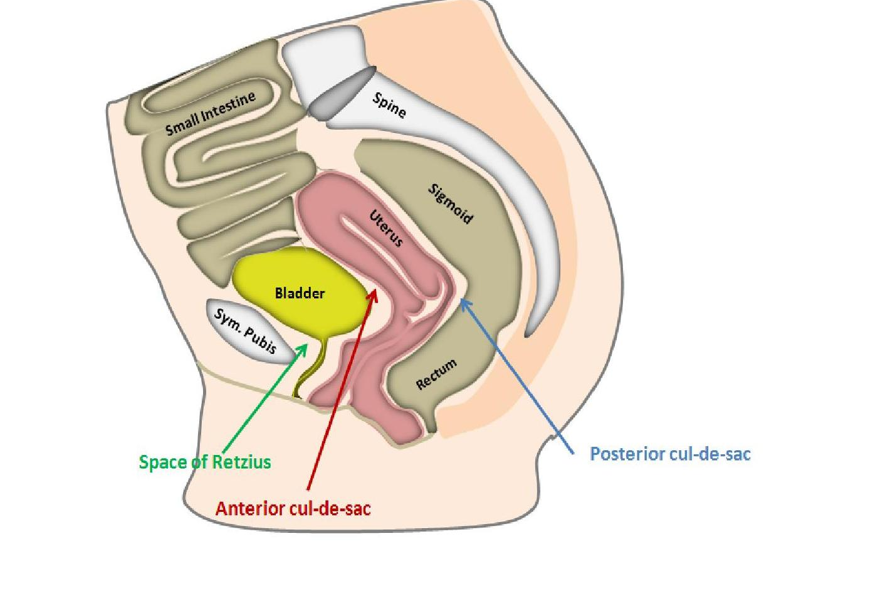

What is another name for anterior cul de sac?

vesicouterine pouch

What is another name for posterior cul de sac?

pouch of douglas

rectouterine pouch

What is another name for space of retzius?

prevesical

retropubic space

The space of retzius is located between the ___ and ___

pubic symphysis; bladder